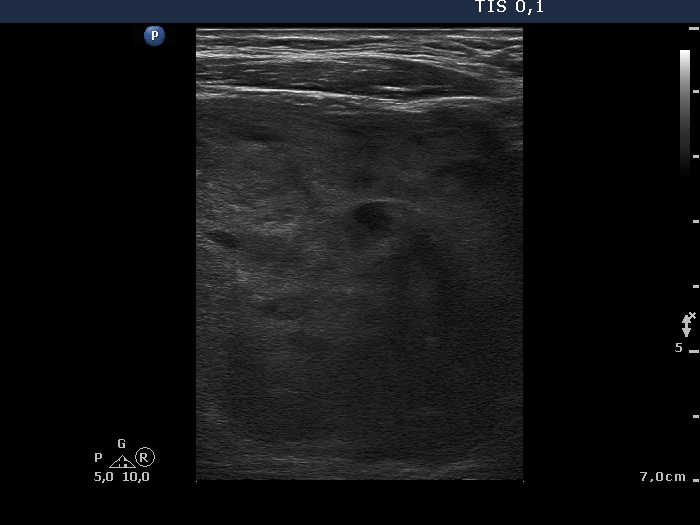

Ultrasonography. The right thyroid was composed of multiple discrete lesions with different echogenicities. The lobe was extremely enlarged with the dimension of 55x65 xminimum 120 mm (width, depth, and length, respectively) and spread retotracheal and substernal. The lower pole of the lobe could not be visualized while swallowing. The left thyroid was normal-sized and contained several hypoechogenic lesions. There was a moderately hypoechogenic nodule in the right lobe. The lesion presented neither halo nor perinodular blood flow.